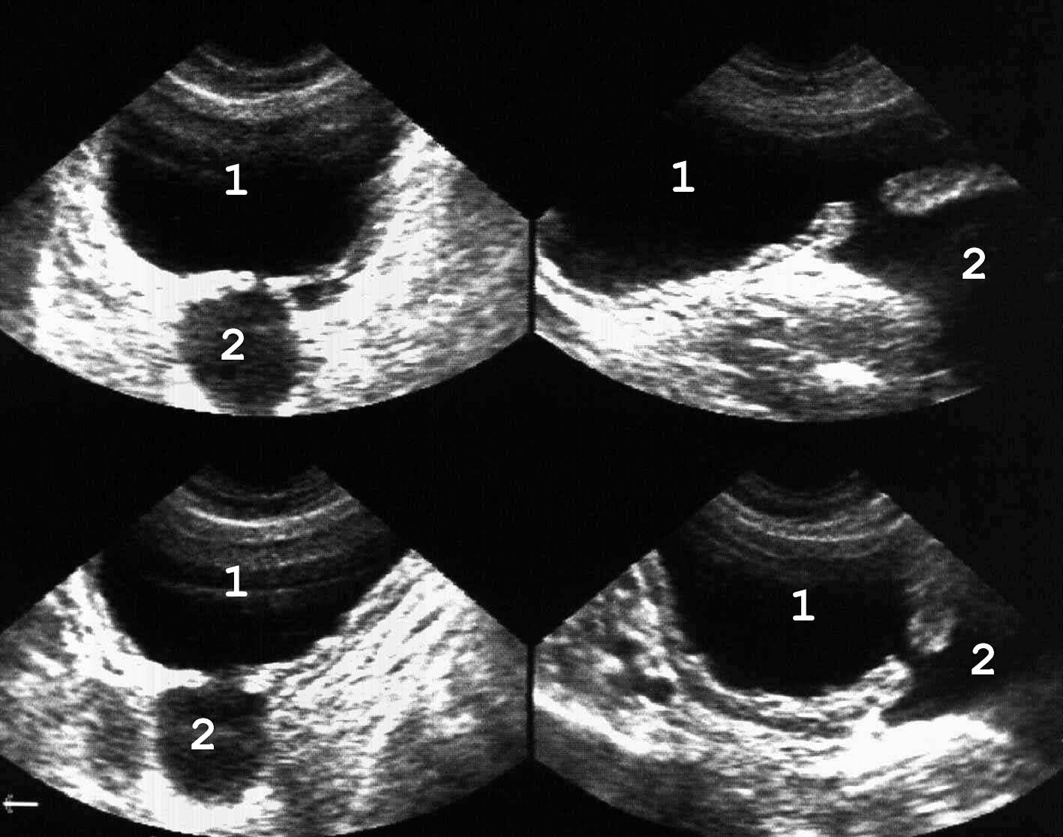

Рис. 12. Множественные дивертикулы мочевого пузыря: 1 − мочевой пузырь; 2 − дивертикулы. (Полипозиционное ска¬ни-рование, секторный датчик 5 МГц, “Siemens SL-1”).

Представляет собой мешковидное выпячивание всех слоев стенки мочевого пузыря вследствие ее непра-вильного формирования (рис. 12). Дивертикулы могут быть одиночными и множественными, чаще располагаются на стенках латеральнее области треугольника, реже − на верхушке или у дна.

Дивертикул сообщается с полостью пузыря узким каналом и нередко имеет большие размеры, иногда превосходящие объем мочевого пузыря. Застой мочи в дивертикуле может приводить к камнеобразованию и возникновению там опухоли.

Рис. 13. Киста яичника, по размерам сравнимая с мочевым пузырем и симулирующая дивертикул: 1 − мочевой пузырь; 2 − киста. Для дифференциальной диагностики необходимо повторное ультразвуковое исследование после микции. Объем кисты после этого остается прежним, а размеры диверти-кула изменяются. (Продольное сканирование, конвекс¬ный дат-чик 5 МГц, “Logiq-500”).